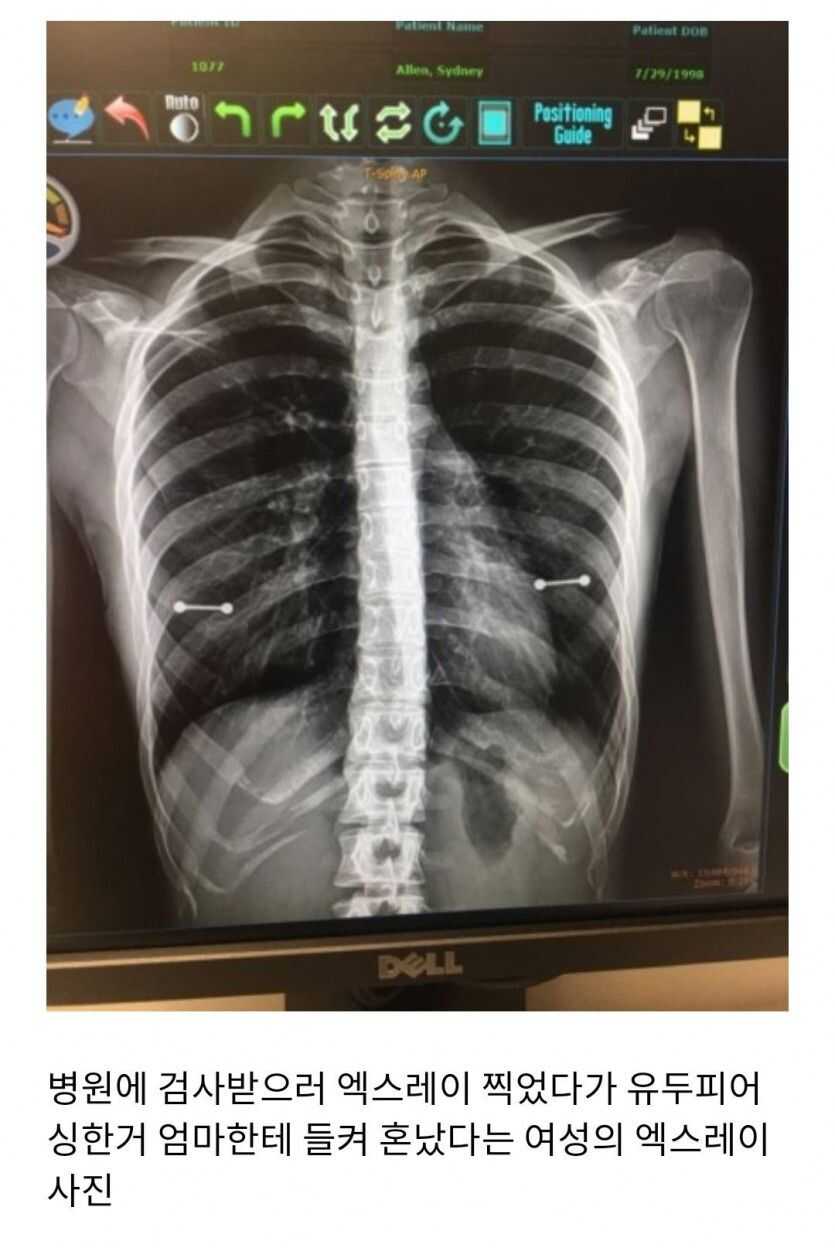

공유 링크 만들기 Facebook X Pinterest 이메일 기타 앱 엑스레이 대참사 한쪽이 좀 내려가 있네? 공유 링크 만들기 Facebook X Pinterest 이메일 기타 앱 댓글